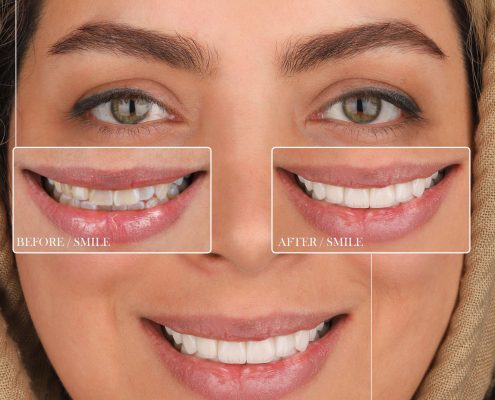

کیس درمانی لمینت سرامیکی

علت مراجعه: نارضایتی بیمار از دندانها در خط لبخند به علت کامپوزیت های قدیمی و معیوب , بهم ریختگی دندان ها

درمان انجام شده: برداشت کامپوزیت های قدیمی و اصلاح بدرنگی ها

طراحی , اصلاح و بهبود خط لبخند برای بیمار

۱۸ واحد لمینیت سرامیکی در دو فک

۱۰ واحد فک بالا

۸ واحد فک پایین